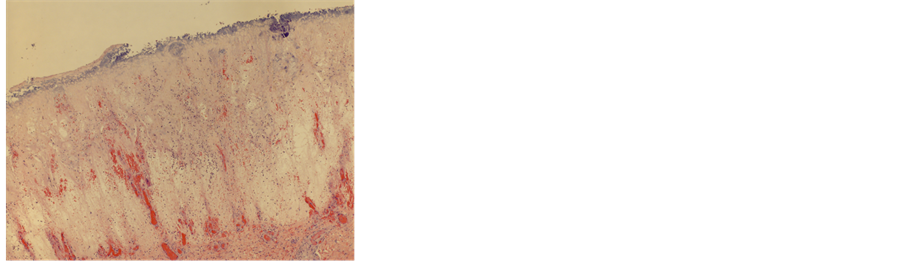

Figure 3. Section of the skin ulcer of the right lower leg revealed denuded squamous epithelium, vascular congestion, marked edema and necrosis (H & E, X 2).

The patient was a 51-year-old African American male with a history of drug abuse. He was found lifeless lying on the kitchen floor at his residence by his wife. An autopsy was performed at the Pathology Department of Louisiana State University Health Sciences Center in Shreveport upon being requested by the local Coroner’s office. Postmortem external examination found multiple old scars (Figure 1), consistent with history of drug abuse, skin abrasions and ulcers of different healing stages over the lower extremities and back (Figure 2). Upon internal examination, the abdominal cavity contained 3600 ml of cloudy ascites. The capsule of the liver was thickened and fibrotic. Other significant findings included cardiomegaly (500 grams, expected 296 - 376 grams) with concentric hypertrophy of left ventricle, nephrosclerosis and severe luminal stenosis of left anterior descending coronary artery. The representative tissue sections taken from their respective organs were fixed in 10% neutral buffered formalin (NBF) for a sufficient time period. Standard hematoxylin and eosin (H & E) stain [8] was performed on the processed paraffin blocks, which contain tissue sections. On microscopy, hematoxylin and eosin (H & E) sections of the skin ulcer of the right lower leg revealed denuded squamous epithelium, marked edema, necrosis (Figure 3) and extensive acute inflammation in cutaneous and subcutaneous tissue (Figure 4). Sections of myocardium and kidney revealed changes consistent with hypertensive changes. Section of liver revealed chronic inflammation in the capsule and subcapsular parenchyma. Cultures of postmortem blood and a swab of soft tissue were positive for Shewanella putrefaciens with antimicrobial susceptibility of ceftazidime, amikacin, piperacillin/tazobactam, cefepime, gentamicin and ciprofloxacin. The cause of death was determined to be sepsis due to hematogenous spread of Shewanella putrefaciens from multiple skin ulcers.